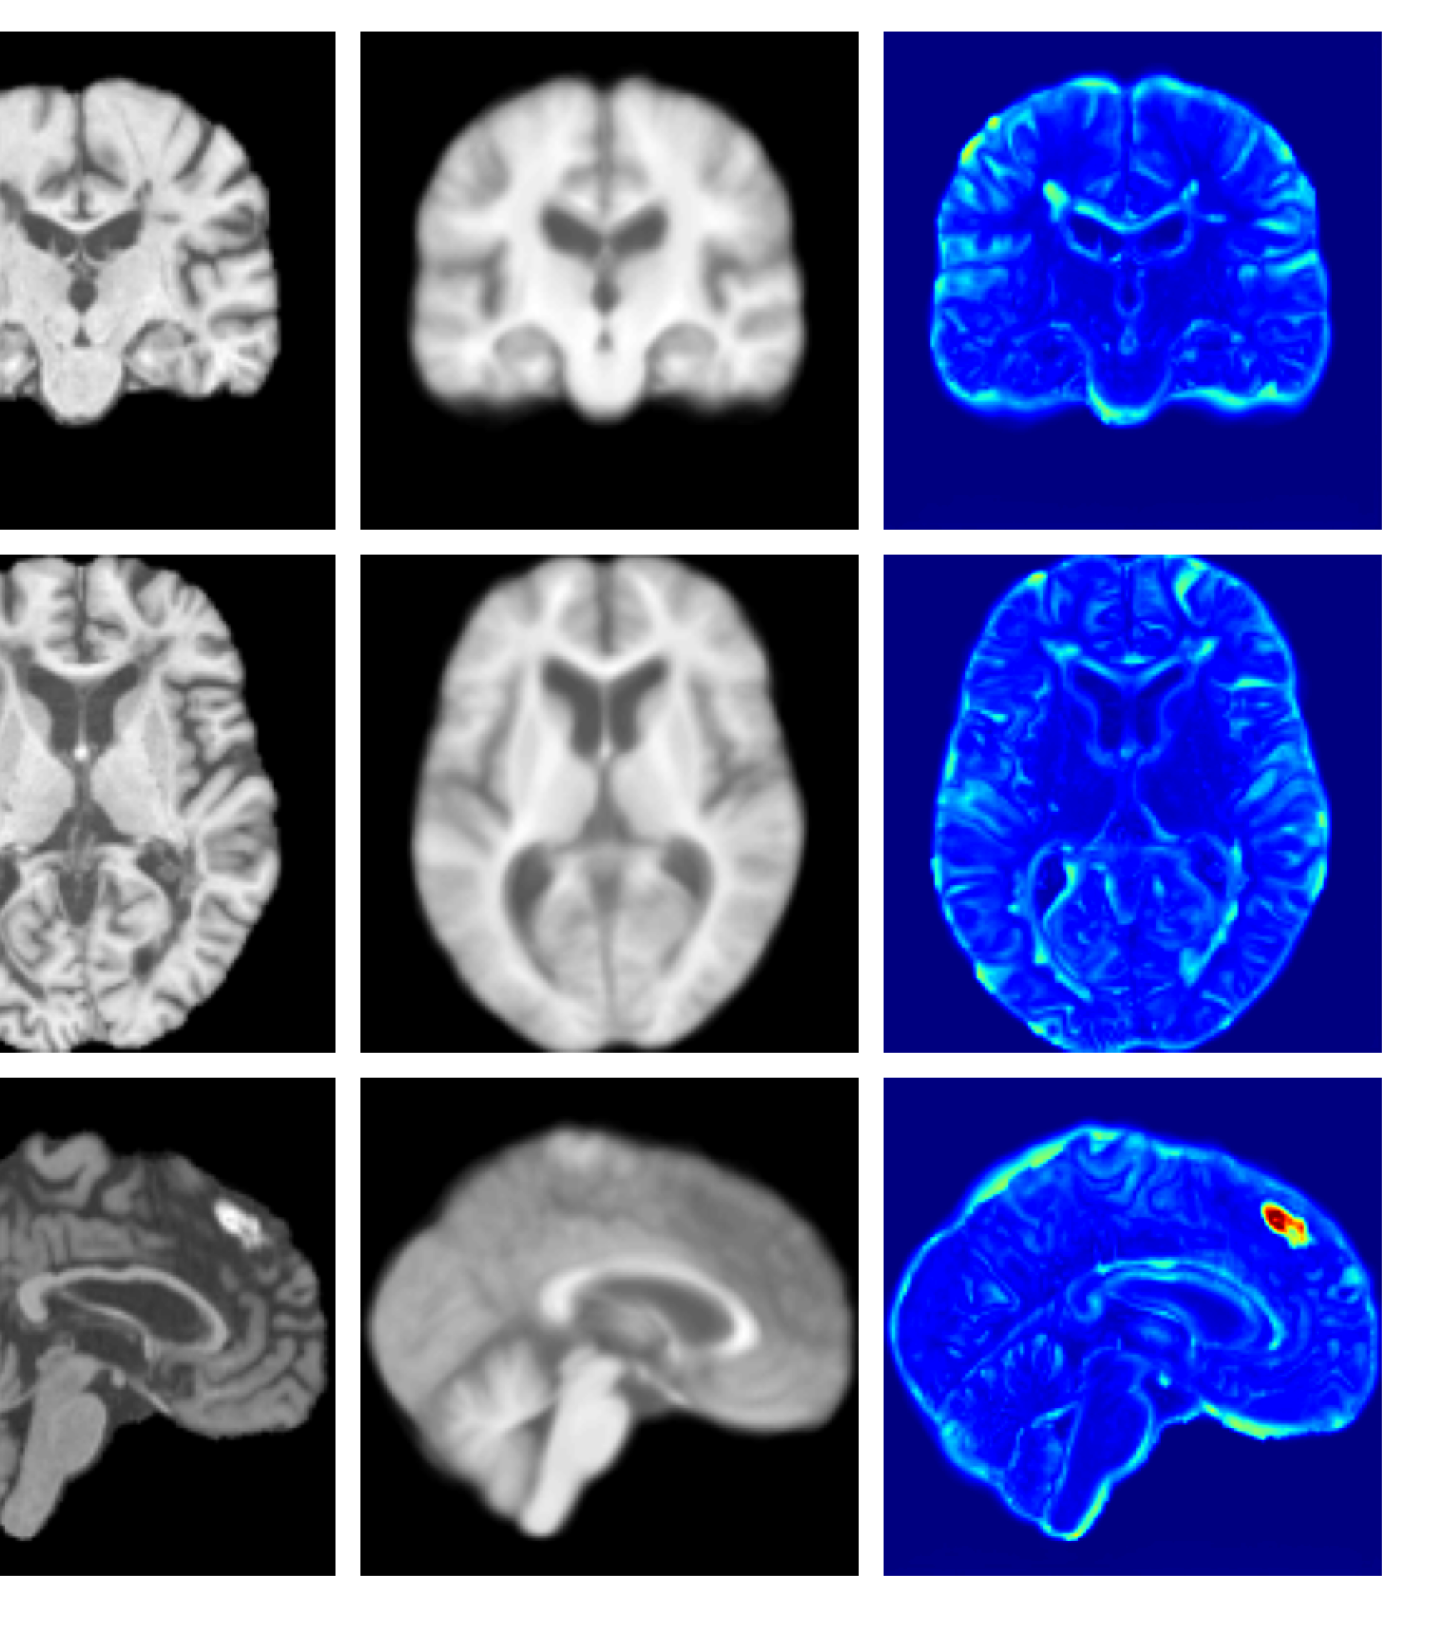

Figure 3: Example reconstructions and anomaly maps for a sample from the disease cohort of the UKBB dataset. Lesion and WMH are indicated in the original image by the red and yellow boxes respectively.

Figures 3 and 4, show example reconstructions and abnormality maps for a sample from the UKBB and UoTH datasets, respectively. Enlarged figures and additional example qualitative results for the ADNI dataset are available in the Supplementary. In Figure 3 we see that whilst all models are able to detect the lesion visible in the sagittal slice, the VAE, cVAE, LDM and LDM (TavgT_{avg}) produce very smooth outputs or lose defining characteristics and thus exhibit more false positives in healthy tissue. THOR and CADD provide the best results, with CADD better detecting white matter hypointensities (WMH). However, neither method fully inpaints all WMH, potentially due to presence of WMH in the healthy training set.

Figures 8 and 9 are enlarged versions of Figures 3 and 4 respectively, with the latter now including results from all compared methods. Figure 10 provides example reconstructions and anomaly maps for an AD subject from the ADNI disease cohort.

Figure 8: Enlarged example reconstructions and anomaly maps for a sample from the disease cohort of the UKBB dataset. Lesion and WMH are indicated in the original image by the red and yellow boxes respectively.